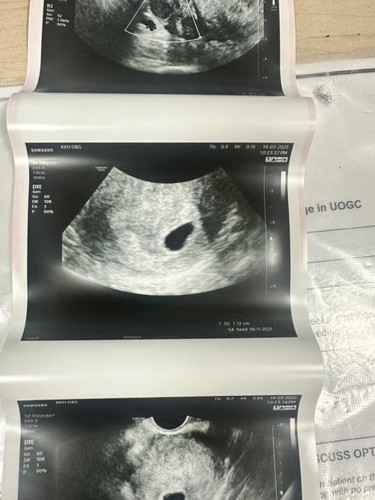

7 weeks pregnancy but only sac is visible

Hi, if counted from my last first menstrual date, then it should be 7th week of pregnancy while I was having my first ultrasound. However, there’s only a gestational sac with size around 1.12cm seen. No embryo yet 🥲 I know that my menstrual cycle is around 33-35 days in average. Anyone has the same experience? Many thanks and hope everyone is enjoying and having a safe pregnancy and parenting journey!

Hi all, Finally I got the answer.. yesterday I had a heavy bleeding with lots of blood clots.. minor cramps also felt as if I am having menstrual cramp.. the bleed continues until today and hasn’t stop.. HCG level dropped and ultrasound showed a shrinked sac.. went to Dr Goh and she said it’s a blighted ovum.. we grieve as a parent to be but it doesnt change the fact that miscarriage is something beyond our control.. Thanks for all the supports and sharings.. this gives me a valuable lesson that pregnancy is tough but worth all the roller coaster of emotions 😊 I am okay and resting well.. hope everyone is expecting have a safe and healthy journey!